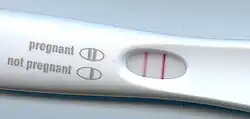

Der Beginn der Schwangerschaft kann erst nach ein paar Tagen nach dem Geschlechtsverkehr auf verschiedene Art und Weise festgestellt werden. In der Abgrenzung zu Scheinschwangerschaften unterscheidet man zwischen unsicheren, wahrscheinlichen und sicheren Schwangerschaftszeichen. Das Ausbleiben der Monatsblutung, morgendliches Erbrechen und Übelkeit sind unsichere Schwangerschaftszeichen. Ein Schwangerschaftstest über die Messung der Konzentration des „Schwangerschaftshormons“ (hCG-Hormon) im Blut oder im Urin gilt als wahrscheinliches, jedoch nicht sicheres Schwangerschaftszeichen. Als sicher gilt der Nachweis eines Fötus, beispielsweise durch Sonografie, das Hören von Herztönen oder Fühlen von Kindsbewegungen.